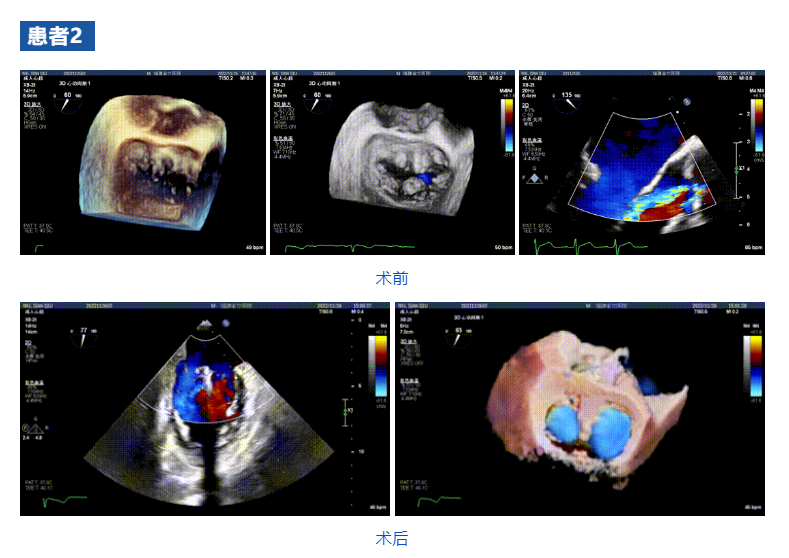

近日,福建省立醫(yī)院心內(nèi)科郭延松教授心臟瓣膜介入治療團(tuán)隊(duì)聯(lián)合浙江大學(xué)醫(yī)學(xué)院附屬第二醫(yī)院王建安教授團(tuán)隊(duì),在福建省首次應(yīng)用JensClip經(jīng)導(dǎo)管瓣膜夾系統(tǒng)為三例二尖瓣重度反流患者開展經(jīng)導(dǎo)管二尖瓣緣對(duì)緣修復(fù)手術(shù)。手術(shù)獲得圓滿成功,患者重獲“心”生。術(shù)后即刻顯示二尖瓣反流顯著改善,術(shù)畢即刻拔管,患者恢復(fù)良好。此次介入手術(shù)的成功再次標(biāo)志著福建省立醫(yī)院心內(nèi)科郭延松教授心臟瓣膜團(tuán)隊(duì)在二尖瓣重度反流修復(fù)介入治療研究領(lǐng)域取得了進(jìn)一步提升,為二尖瓣重度反流患者帶來更多的臨床獲益。

接受治療的三例患者均為器質(zhì)性重度二尖瓣反流(DMR)患者,術(shù)前超聲提示二尖瓣后葉脫垂伴4+反流,左室舒張功能減退。郭延松教授攜同團(tuán)隊(duì)成員陳新敬副教授和洪景宣、方明程、楊清勇主治醫(yī)師、心外科丁杭主任以及超聲科賴寶春、葉振盛主治醫(yī)師共同進(jìn)行病情討論??紤]到患者高齡、基礎(chǔ)疾病多、STS評(píng)分高,為外科手術(shù)極高危患者,不適合進(jìn)行外科開胸二尖瓣手術(shù),因此決定為患者實(shí)施經(jīng)導(dǎo)管緣對(duì)緣修復(fù)介入術(shù)(JensClip經(jīng)導(dǎo)管瓣膜夾系統(tǒng))。

在浙江大學(xué)醫(yī)學(xué)院附屬第二醫(yī)院王建安教授團(tuán)隊(duì)的支持下,手術(shù)經(jīng)股靜脈-房間隔入路,采用全身麻醉插管,在TEE和DSA引導(dǎo)下完成房間隔穿刺。置入JensClip瓣膜夾系統(tǒng)后,在左房調(diào)整瓣膜夾的位置和軸向,后進(jìn)入左室,在TEE引導(dǎo)下捕捉二尖瓣前后瓣葉,并關(guān)閉瓣膜夾。經(jīng)TEE反復(fù)確認(rèn)手術(shù)效果后最終鎖定并釋放瓣膜夾。術(shù)后即刻超聲顯示瓣膜夾位置穩(wěn)定,功能良好,二尖瓣反流由術(shù)前4+減少至微量,手術(shù)圓滿成功。